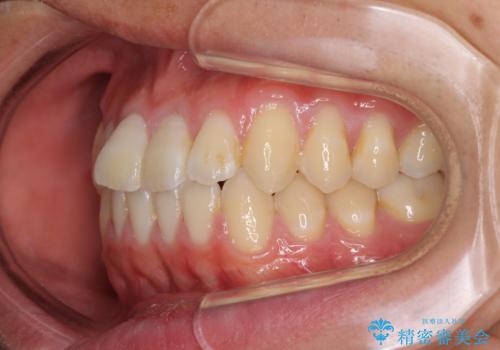

- 上下前歯のデコボコを気にして来院された患者様です。

叢生は軽微であり、費用を抑えて期間もあまりかけずに治療をしたいとのことで、インビザライン・ライトを用いて矯正治療を行うこととしました。

途中通院できなくなり、マウスピースの装着もしっかりとできなかったため、治療期間が長くかかってしまいました。